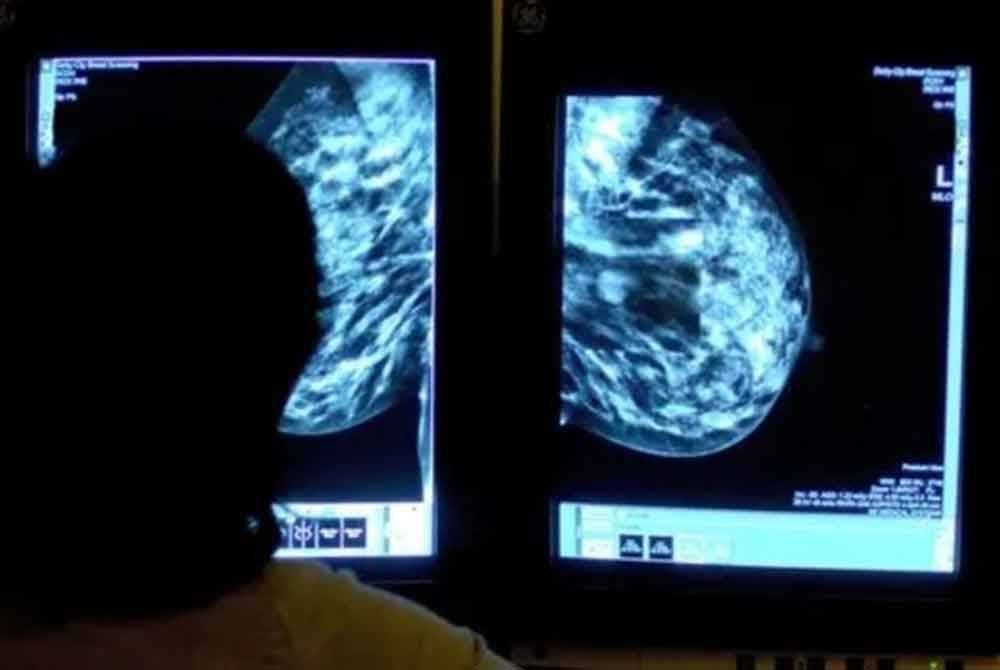

Ujian penyaringan kanser payudara menggunakan AI bertujuan mempercepatkan diagnosis dan mengurangkan tekanan kepada pakar radiologi, lapor BBC.

Pada masa ini, dua pakar radiologi meneliti mamogram untuk ketepatan. Sistem AI berkemungkinan membolehkan seorang pakar sahaja menyelesaikan proses tersebut, membantu mengurangkan masa menunggu.